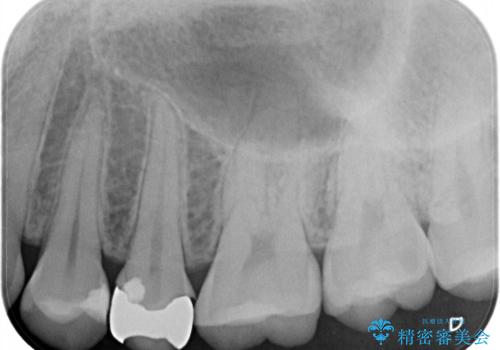

他院で虫歯治療を複数行っており、原因となりうる歯がいくつかありました。まずレントゲン上最もあやしい右上から治療開始しました。

右上の被せものを除去したところ、中で歯が割れていたため、部分矯正で引っ張り出すことになりました。